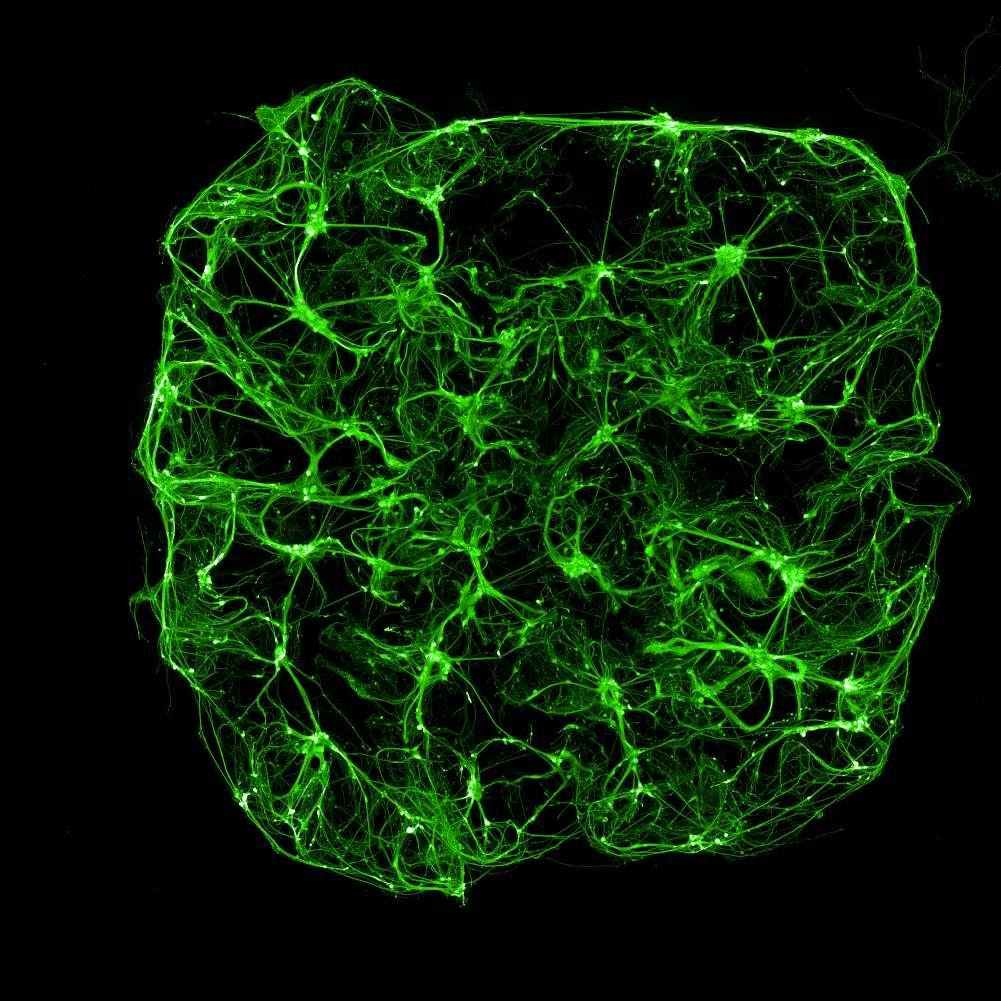

Calceinlabellingofneuron-astrocytecoculturesatmultipletimepointsshowedrobustcellviabilityandincreasedculturecomplexityovertime.

1week7weeks

•Wehavesuccessfullydemonstratedthata3Dmodelof neuronsandastrocytesareabletogrowandremain viableforupto8weeks.

•The3Dmodelisamenableforbothfixedandlivecell imaging(e.g.viability,neuronalactivity,mitochondrial function).

•WehaveestablishedaCNStriculturemodelinwhich microgliaareinvadingthegelandmigratingtowards neuronsandastrocyte.